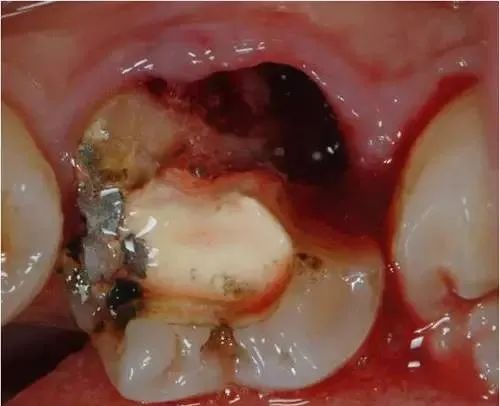

事实上,做完根管治疗后的牙齿,没有了牙髓供给营养,牙齿会变得十分脆弱,剩余的牙齿部分很容易劈裂,下图就是牙医接诊的根治后没做冠的患者,劈裂的牙齿是不是很可怕?

因此根管治疗后一定要做个牙冠将其保护起来。